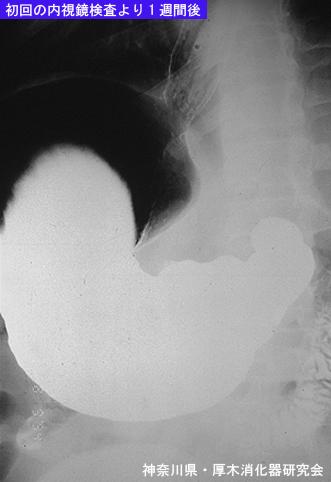

A case of gastrin anisakis mimicking a type IIc early gastric cancer (1980's).

[ Image ID:5803 ]

Gastrointinal Parasite/Anisakis

Stomach/Other

X-ray